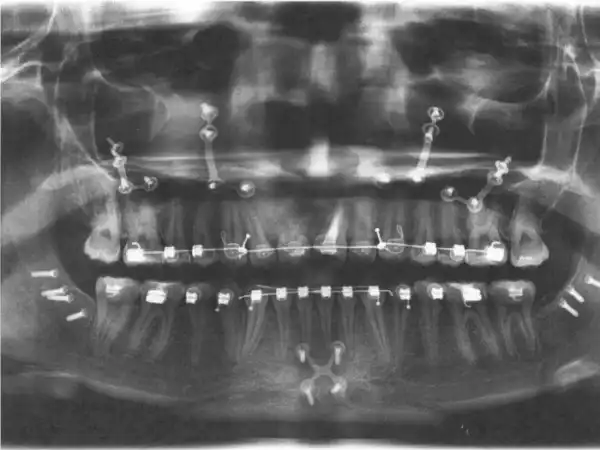

Этой девушке давно пора было исправить свой прикус, поэтому она обратилась к стоматологу.

Врач установил ей специальные брекеты, которые ей придется носить долгих пять лет.

Но, что поделаешь, за красоту надо платить.

Судя по титановым пластинам на рентгенограмме, ей ещё операцию делали на нижней и верхней челюстях. нижнюю челюсть точно в трех местах пилили